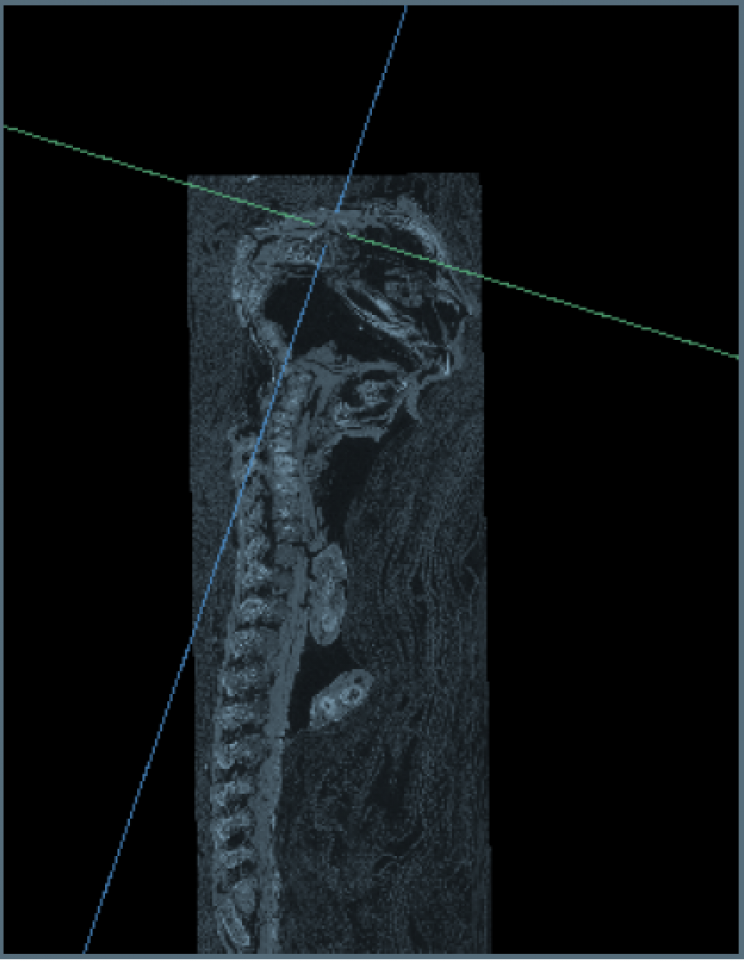

Sự thật chỉ được hé lộ khi Andrew Nelson - nhà khảo cổ sinh vật học và giáo sư ngành nhân chủng học tại Đại học Western Ontario cùng các cộng sự đã thực hiện nghiên cứu xác ướp bằng kỹ thuật chụp cắt lớp vi tính (micro CT scanning) và phát hiện bí mật bất ngờ.

Cụ thể, kết quả kiểm tra cho thấy xác ướp tí hon mà mọi người cứ nghĩ là của diều hâu lại là một đứa trẻ chết yểu khi 23 - 28 tuần tuổi.

Thi hài bé trai này chết non là trường hợp hiếm gặp vì não và hộp sọ cậu bé đã không thể phát triển. Toàn bộ phần đầu hộp sọ đã không được thành hình. Thêm nữa, các đốt sống của cậu bé đã không khít với nhau và tiểu cốt nhĩ lại nằm phía sau đầu.

Theo nhà khảo cổ Nelson, xác ướp bé trai này là một trong 2 xác ướp duy nhất được phát hiện ở Ai Cập mắc phải hội chứng Anencephaly (thiếu một phần não khi sinh).